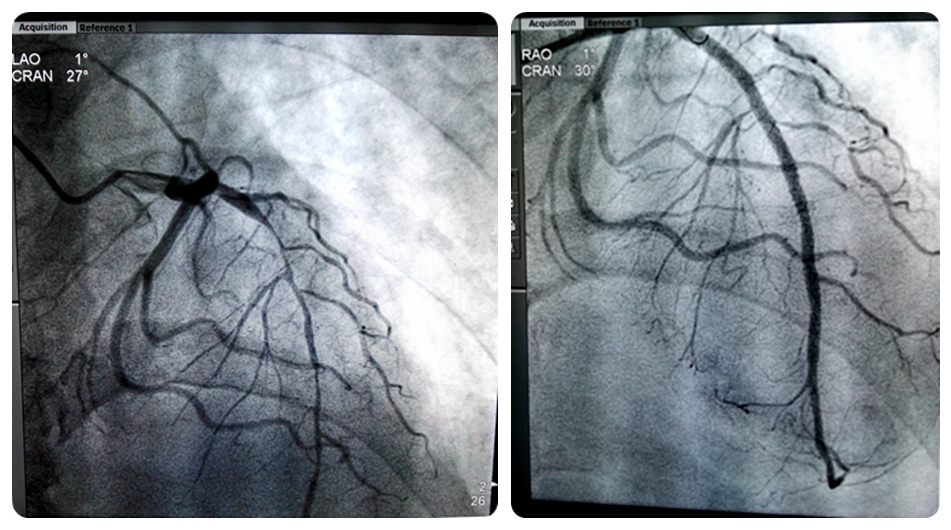

20日上午,在心内科主任彭道地教授的指导下,范爱德副主任医师、王鹏主治医师及龚辉医师为患者实施了心脏冠脉造影术+支架植入术,护理部文娟护士长、刘秋容及刘玲慧护士积极配合。手术采用桡动脉路径,首先在病人手腕处做了一个3mm的小切口,行左右冠状动脉造影检查,造影显示:冠状动脉多支多处严重狭窄病变,其中前降支近中远段弥漫狭窄85-99%,可见血流慢,明确显示前降支就是这次发生心梗的“罪犯”血管。前降支狭窄病变严重,需行PCI术。术中发现前降支球囊扩张后无复流,予以替罗非班和硝酸甘油冠脉内给药,并在病变处植入2枚药物涂层支架。支架术后恢复血流灌注。整个手术顺利,从患者进入导管室到手术完毕只用了60分钟。患者及家属对湘雅常德医院的技术水平及服务态度相当满意。

手术前后对比图